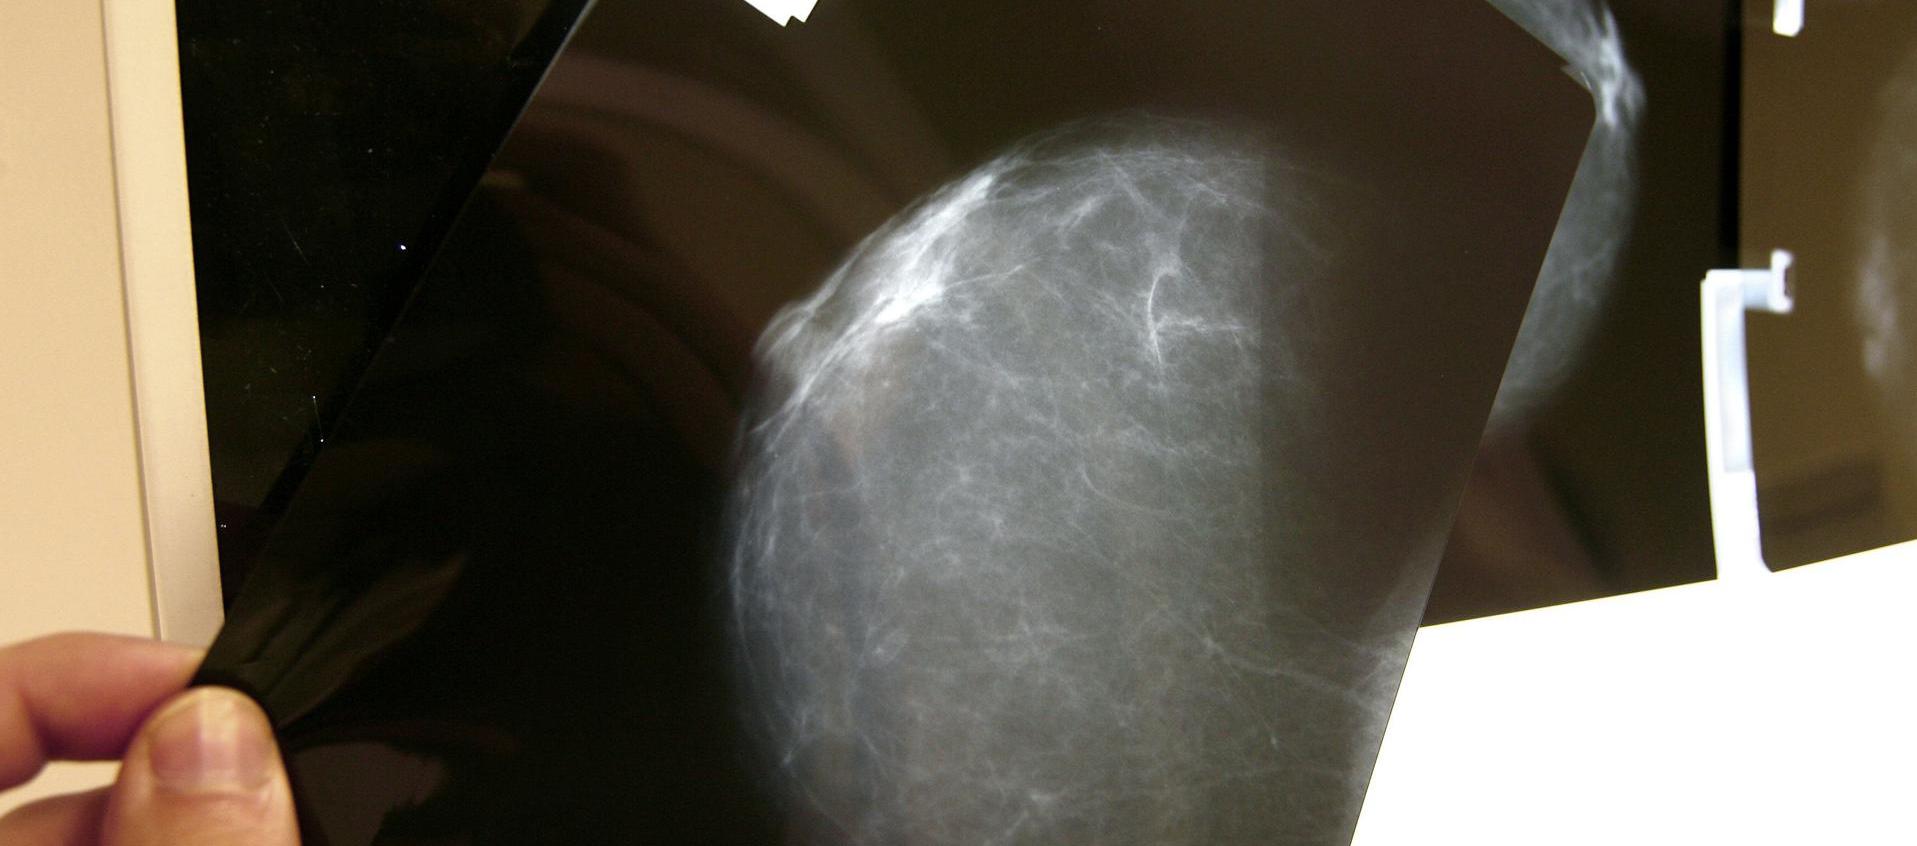

Ecografía mamaria

Foto

EFE